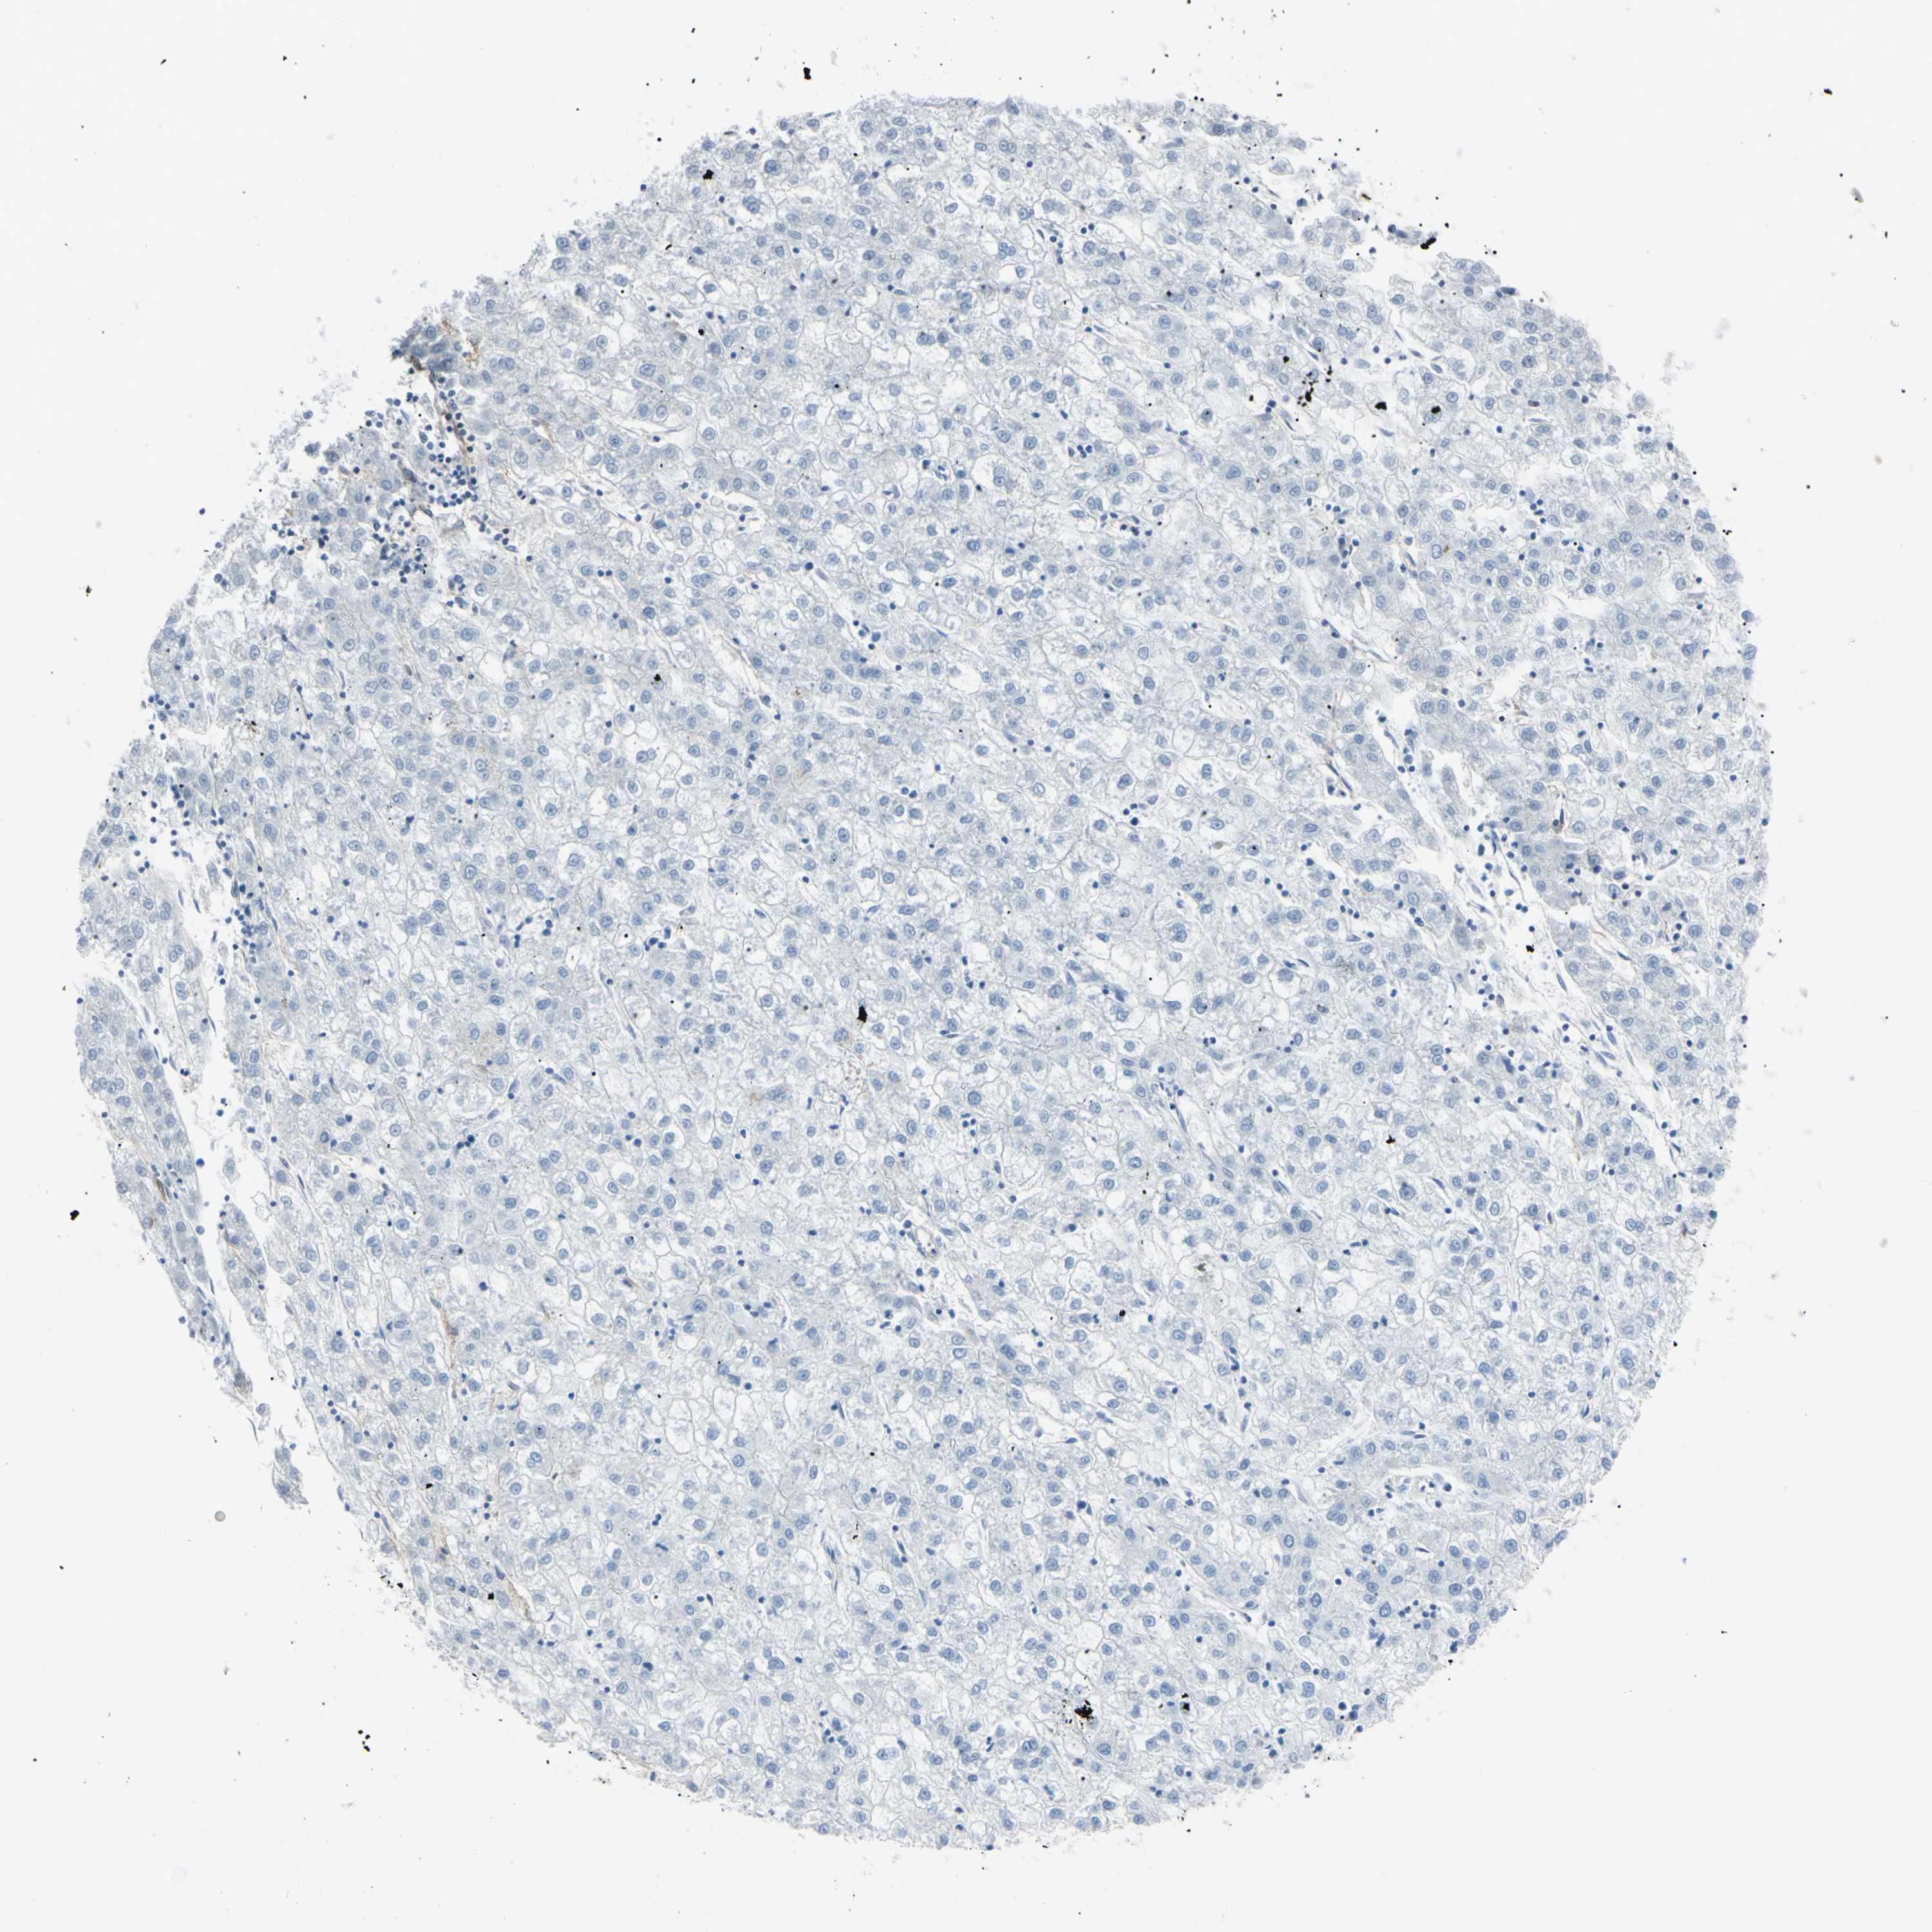

LIVER CANCER - Protein expressioni

A mouse-over function shows sample information and annotation data. Click on an image to view it in a full screen mode. Samples can be filtered based on level of antibody staining by selecting one or several of the following categories: high, medium, low and not detected. The assay and annotation is described here.

Antibody staining in the annotated cell types in the current human tissue is reported as not detected, low, medium, or high, based on conventional immunohistochemistry profiling in selected tissues. This score is based on the combination of the staining intensity and fraction of stained cells.

Each image is clickable and will lead to virtual microscopy that enables deeper exploration of all samples and also displays staining intensity scores, fraction scores and subcellular localization as well as patient and tissue information for each sample.

Antibody HPA010593

Staining

High

Medium

Low

Not detected

Intensity

Strong

Moderate

Weak

Negative

Quantity

>75%

75%-25%

<25%

None

Location

Nuclear

Cytoplasmic/membranous

Cytoplasmic/membranous,nuclear

Cholangiocarcinoma

Carcinoma, Hepatocellular, NOS